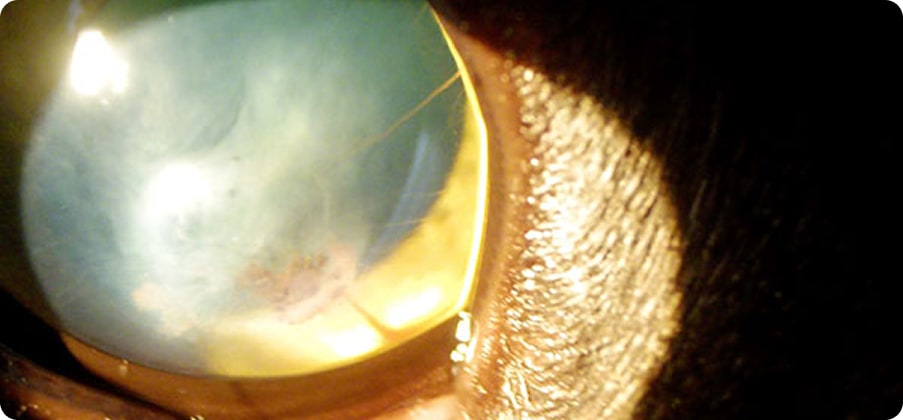

目の中にある「水晶体(すいしょうたい)」が白く濁ってしまう病気です。

水晶体は、カメラでいうレンズのような働きをしており、本来は透明で光を通して物を見るために重要な部分です。

時間経過と共に白内障は進行していき、やがては緑内障やぶどう膜炎など他の眼疾患を引き起こす原因になります。

そのため早期の治療が望まれる病気です。

大型犬では6歳くらい、小型犬では10歳くらいが発症しやすいですが、若齢の子でも発症することもあります。

さまざまな原因が存在します。代表的なものとして、遺伝によるもの、代謝によるもの、ほかの疾患から続発して起こるものがあげられます。

アメリカンコッカースパニエル、トイプードル、パピヨン、ボーダーコリー、チワワ、柴犬、シーズー、ゴールデンレトリーバー、ラブラドールレトリーバーなどがなりやすいと言われています。

糖尿病のわんちゃんなどは体内の糖分を上手く利用することが出来ないため、水晶体に水が溜まり、混濁を引き起こしてしまいます。このように代謝の異常で白内障が引き起こされることがあります。

水晶体の脱臼、ぶどう膜炎(目の奥の炎症)、緑内障などの病気や状態が二次的に水晶体を白濁させる原因になります。この他にも、外傷や様々な薬剤などが原因となることもあります。

現在は薬による治療は、ほとんど効果がありません。そのため、外科手術が主な治療となります。

白内障が進行すると、水晶体を包む皮が破れて中身が外に漏れ出してしまいます。 すると体の免疫が異物と判断して強く反応し、眼の中で炎症が起きます。これを「水晶体起因性ぶどう膜炎」といいます。炎症を抑えるためには毎日点眼薬が必要になり、わんちゃんも飼い主様も大きな負担になります。 視覚が一時的に回復しても、眼の中では炎症が進んでいて、痛みや不快感を感じていることがあります。さらに、緑内障や網膜剥離といった重い病気を引き起こし、最悪の場合は失明につながることもあります。 そのため、早期発見と治療がとても大切です。

白内障は水晶体の混濁の程度で4つのステージに分類されます。

成熟白内障

過熟白内障

混濁は15%以下で目は見えている状態。

混濁は15%以上で目は見えている~見えづらい状態。

全体的に混濁し、目が見えない状態。

水晶体の中身が漏れ出ることで、混濁は薄くなり目は見えづらい〜少し回復し見えている状態。